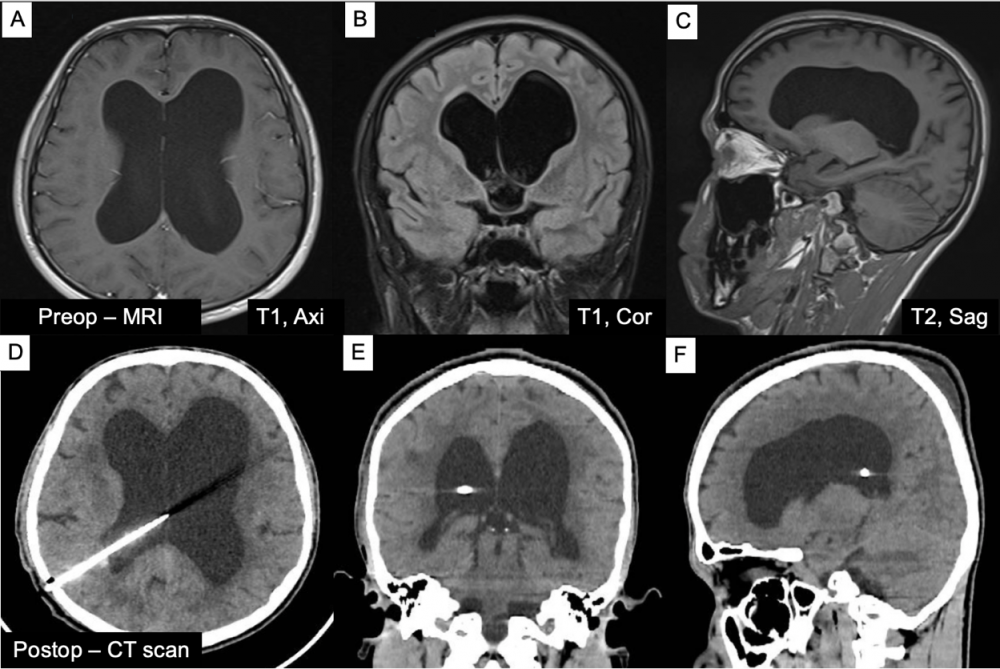

Hình 2. Hình ảnh cộng hưởng từ giãn não thất trên mặt phẳng cắt ngang, đứng ngang, đứng dọc (A-C) và hình ảnh cắt lớp vi tính 1 ngày sau phẫu thuật dẫn lưu não thất ổ bụng (VP shunt), shunt đúng vị trí trên các mặt phẳng (D-F)

Bệnh nhân nam 24 tuổi nhập viện vì đau đầu và chóng mặt kéo dài. Triệu chứng xuất hiện tăng dần sau một tai nạn giao thông khoảng 3 tháng trước, lúc đó bệnh nhân được chụp CT scan và tình cờ phát hiện giãn toàn bộ hệ thống não thất nhưng không điều trị gì. Khám lâm sàng, bệnh nhân chỉ đau đầu âm ỉ, tăng khi thay đổi tư thế, không có dấu hiệu thần kinh khu trú, không rối loạn tri giác; Glasgow 15 điểm, không yếu liệt, không rối loạn thị giác hay vận nhãn, không hội chứng tăng áp lực nội sọ rõ ràng. Bệnh nhân dược chỉ định phẫu thuật dẫn lưu não thất ổ bụng (VP shunt), sau phẫu thuật tình trạng đau đầu và chóng mặt giảm dần, không ghi nhận biến chứng sau phẫu thuật, bệnh nhân ra viện sau 7 ngày.

- Ở người trẻ, EI = 0.48 như trường hợp này cho thấy giãn não thất rõ rệt